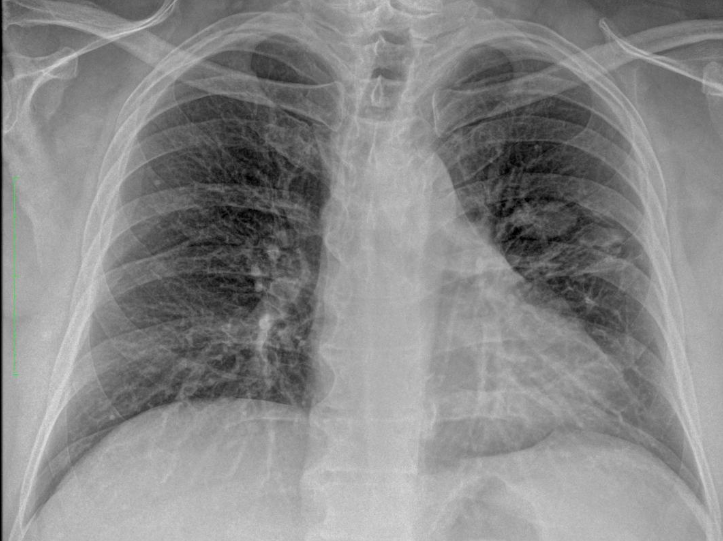

draurtecho Ago 27, 2024 Las técnicas de diagnóstico por imágenes son fundamentales para el diagnóstico de la enfermedad pulmonar. Las radiografías de tórax, las ecografías pulmonares y las tomografías computarizadas ofrecen ventajas y limitaciones únicas. Reconocer patrones radiológicos específicos es útil para identificar patógenos y orientar el tratamiento. No Comments InNeumología